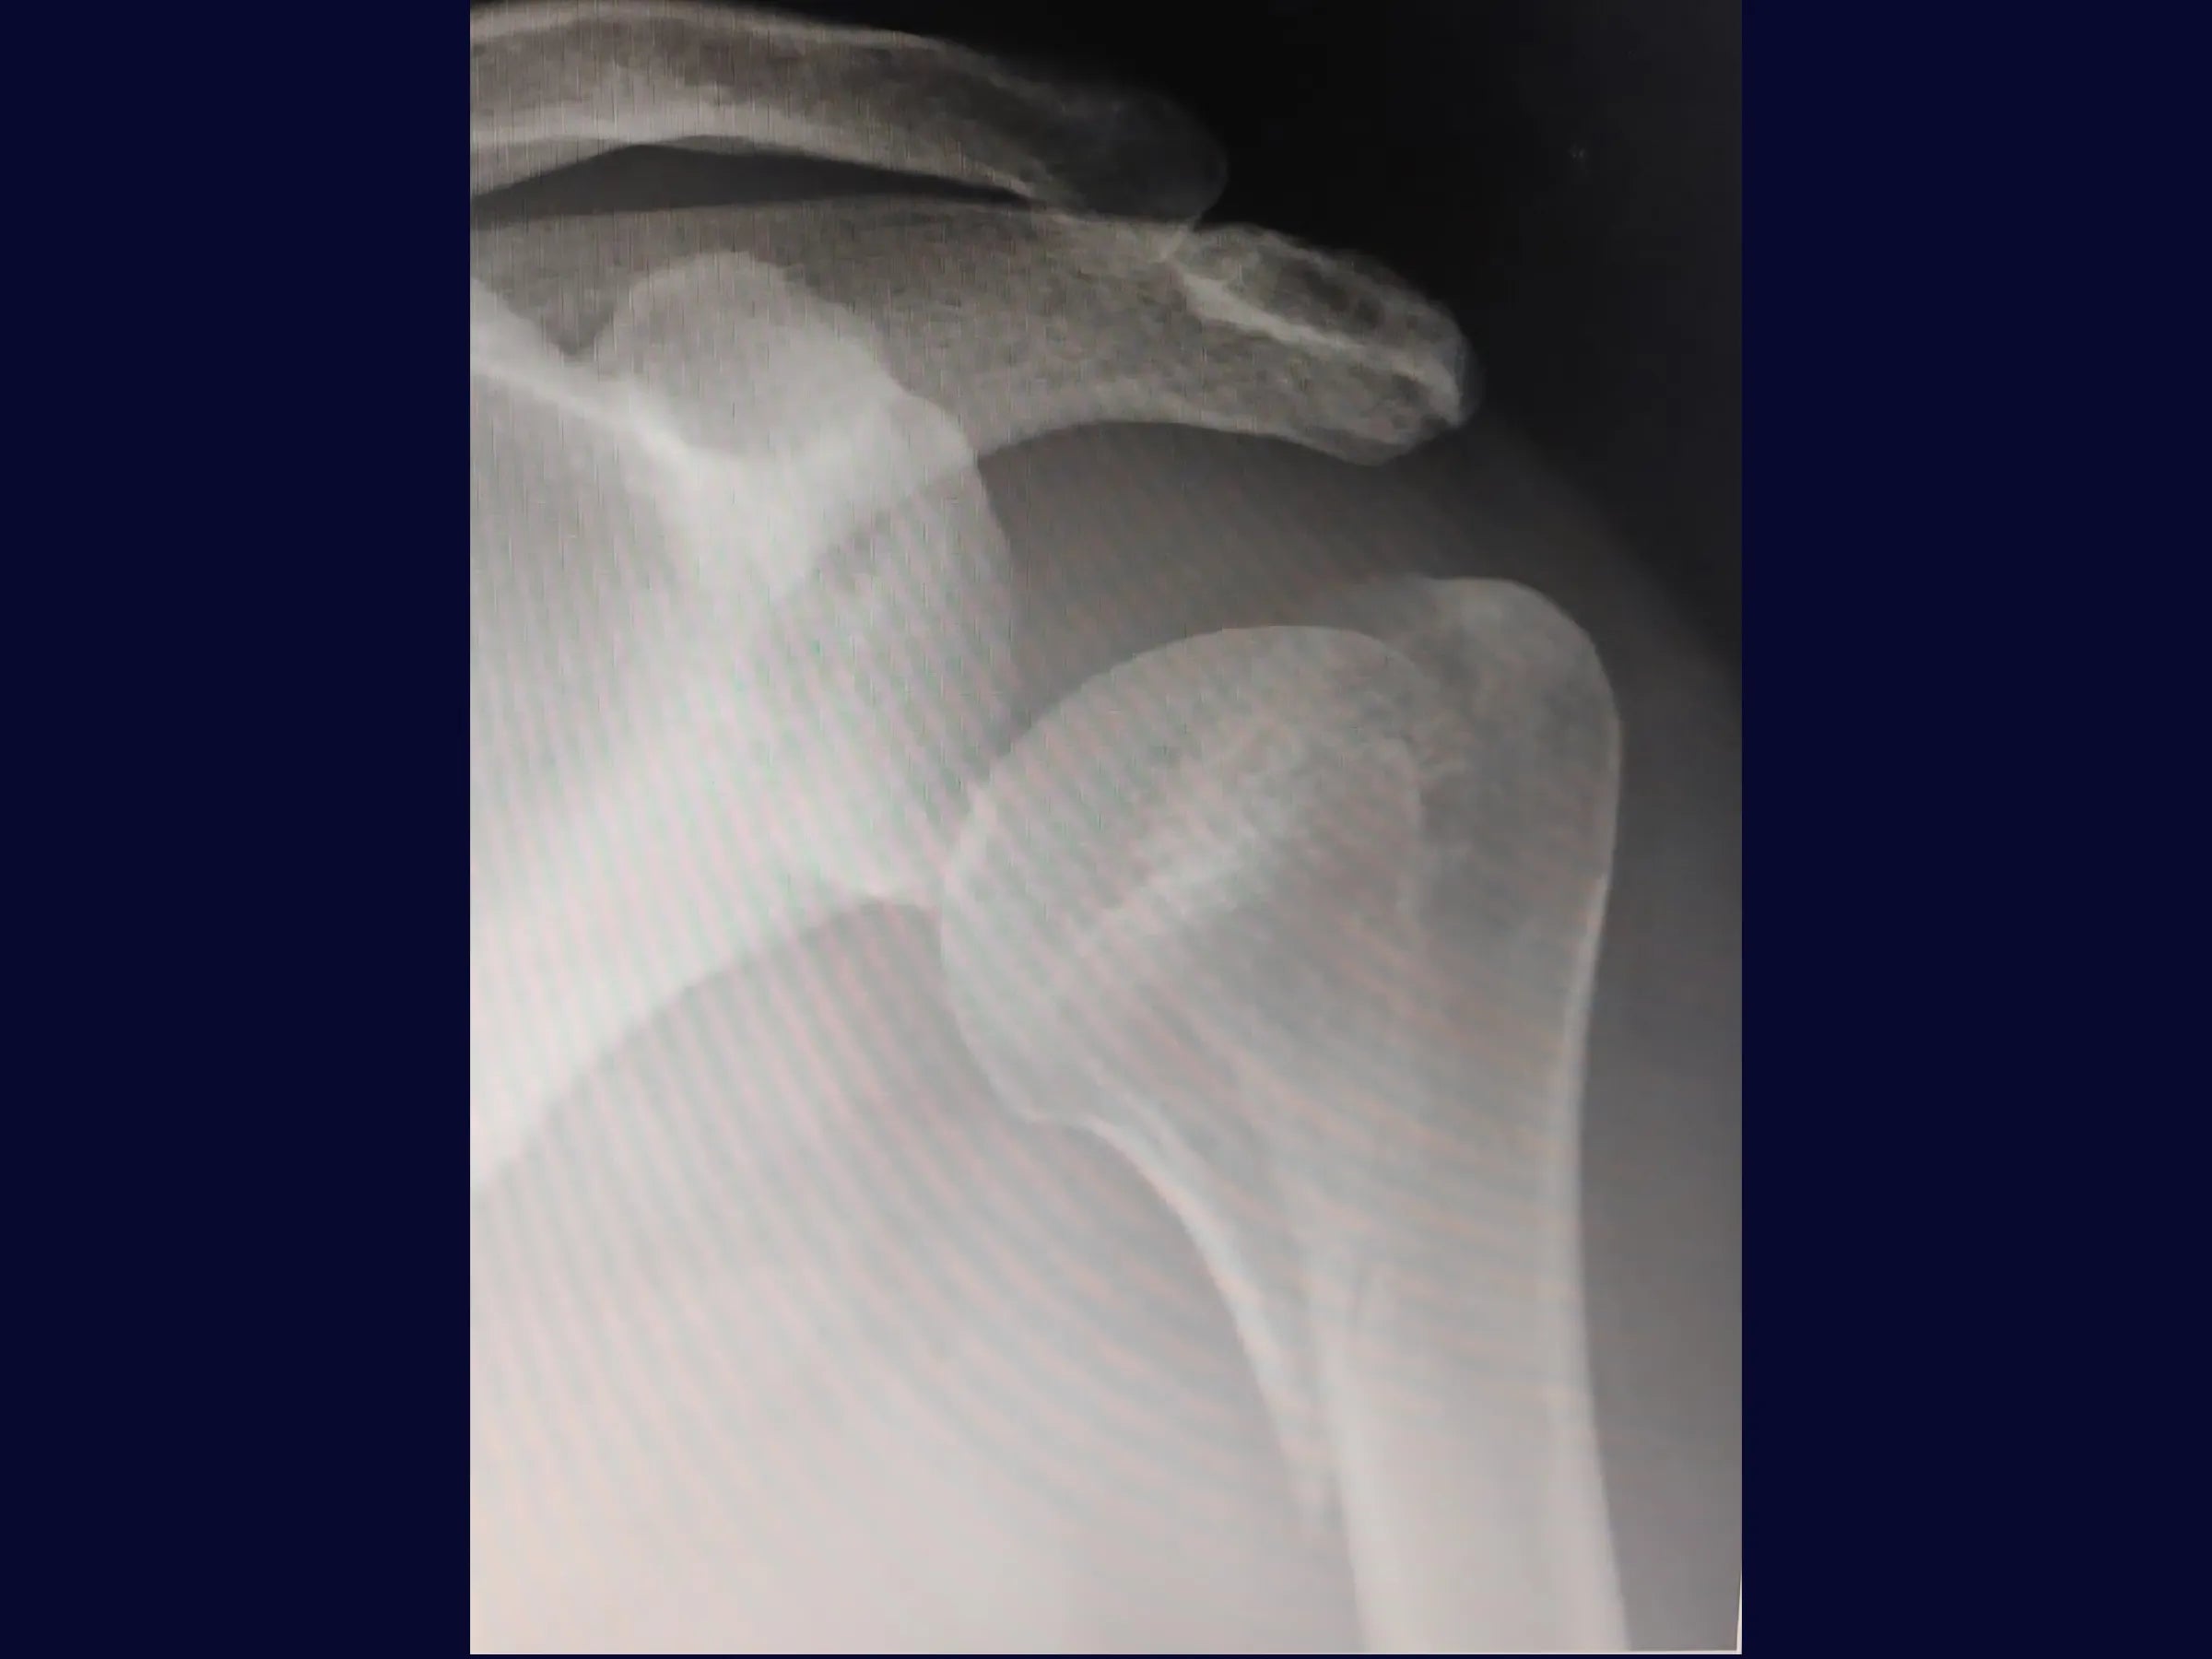

A consolidação parcial em fraturas proximais do úmero com cisalhamento medial representa um desafio frequente na prática ortopédica, dificultando a redução anatômica e a estabilização adequada.

- Redução indireta de fratura proximal do úmero com cisalhamento medial.

- Redução Indireta com Placa: Uso da própria placa como alavanca para superar consolidação parcial e restaurar a altura da cabeça umeral.